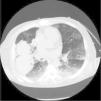

Ante sospecha de vasculitis, se inició tratamiento con 3 bolos de metilprednisolona de 500mg en días consecutivos y, posteriorment,e prednisona a 1mg/kg cada 24h. A las 72 h se produjo un cuadro de hemoptisis y anemización: se realizó radiografía de tórax y TAC torácica que mostraron hallazgos sugestivos de hemorragia alveolar bilateral y presencia de hematoma pulmonar intraparenquimatoso (figs. 1 y 2). Se inició tratamiento con bolos de 500mg/m2 de ciclofosfamida e inmunoglobulinas a 2 g/kg repartidas en 5dosis. Cinco días después apareció hemoptisis franca, anemización y gran trabajo respiratorio con traslado a UCI, donde se procedió a intubación orotraqueal y ventilación mecánica; el paciente precisó aspiración por sangrado masivo.

Las radiografías de tórax suelen ser inespecíficas: se precisa tomografía computarizada para confirmar los hallazgos. La gravedad de la situación justifica el uso del tratamiento inmunosupresor intensivo9: es habitual un tratamiento combinado con glucocorticoides y ciclofosfamida, azatioprina, metotrexato o rituximab. También se ha constatado la plasmaféresis como opción terapéutica.